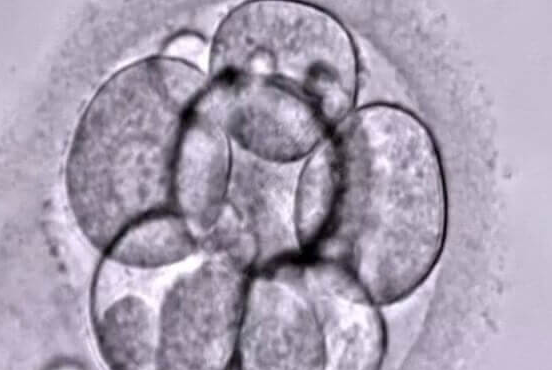

吉尔吉斯斯坦三代试管婴儿(PGT)技术对标美国标准,NGS 高通量测序 + AI 胚胎评估双核心,2026 年临床妊娠率达 65%-75%,35 岁以下患者…